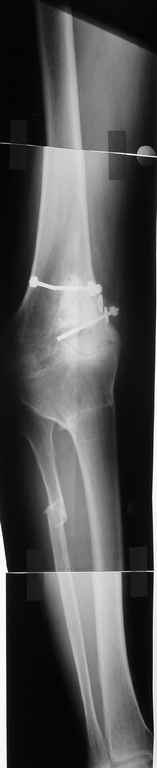

Пациент 59 лет, в 1982 году по поводу остеобластокластомы была выполнена частичная резекция проксимального отдела бедра с пластикой дефекта костно-хрящевым трансплантатом (моноблок)с фиксацией металлическими стяжками.

В последующем по поводу деформирующего артроза выполнена корригирущая остеотомия большеберцовой кости. Исход представлен на рентгенограмме. В настоящий момент пациента беспокоят боли в коленном суставе, деформация, и ограничение движений. Варусная деформация коленного сустава 20, движения сгибание 115, разгибание 150, ходит с тростью, выраженная хромота, работа не связана с физическими нагрузками. Правый коленный сустав без патологии. Уважаемые коллеги просим высказать своё мнение - артродез коленного сустава или эндопротезирование.